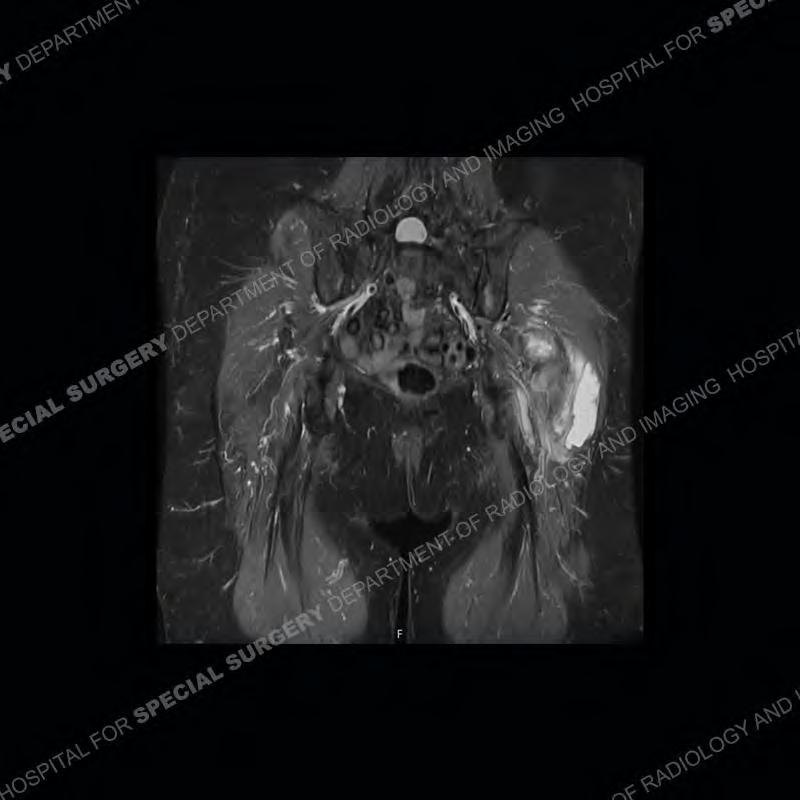

The radiograph is not particularly contributory in this case. The MRI demonstrates markedly abnormal architecture of the gluteus minimus and anterolateral band of the gluteus medius. Portions of the tendons are high signal, portions are highly attenuated, and portions are disrupted. A large, complex fluid collection is present in the adjacent soft tissue.

Diagnosis: Gluteal Tendinosis and Disruption with Complex Trochanteric Bursal Collection

Not as much of a diagnostic dilemma as many of the other cases shown but just a nice example of the pathology seen of the gluteal tendons and a cause of trochanteric pain. Although, frequently thought of in isolation, trochanteric bursitis or bursal thickening is much more commonly a reactive change to underlying pathology of the subjacent gluteal tendons. The gluteus medius is divided into a posterior band and an anterolateral band. Tendinosis and partial tearing very commonly will involve the gluteus minimus and especially the more posterior fibers and then propagate into the anterior lateral band of the gluteus medius. Involvement of the posterior band of the medius is much less common and engenders a marked degree of functional impairment.

The bursae about the greater trochanter can be a little bit confusing especially given the terminology. Trochanteric bursitis is implied to mean the subgluteus maximus bursa which is present deep to the maximus and just lateral/superficial to the trochanter. That is the bursa involved in this case. In this case the complexity of the bursa relates to the tendon tearing with inflammatory change and probably hemorrhage accounting for the complexity. Two other, less frequently involved bursa are also present. The subgluteus medius and subgluteus minimus bursa are found just deep to the named tendons. Although pathology does frequently follow the previously described pattern it is possible to have isolated pathology to either the medius or minimus.